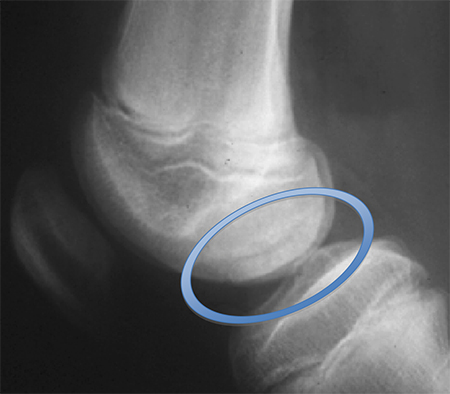

Preoperative radiograph with large osteochondritis lesion of the femoral condyle

From the collection of H. Chambers, MD